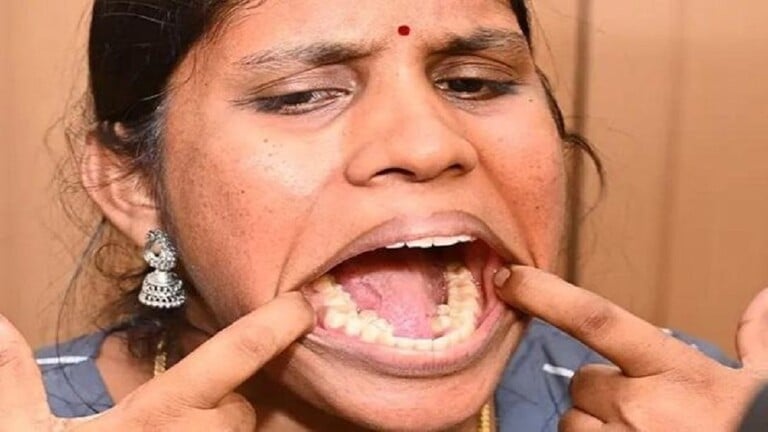

دخلت امرأة هندية (26 سنة) موسوعة غينيس للأرقام القياسية بعد التأكد من أن في فمها 38 سنا، أي لديها ستة أسنان أكثر من عدد الأسنان الطبيعي الموجود لدى معظم البشر.

وقد اتضح أن للشابة كلبانا بالان صاحبة الرقم القياسي، أربعة أسنان إضافية في فكها السفلي واثنان في فكها العلوي. وبدأت الأسنان الزائدة تنمو في صغرها، ولم يزعجها الألم، لكن والداها أصرا على مراجعة طبيب الأسنان ليخلع الأسنان الزائدة. إلا أنها خافت وقررت ترك كل شيء كما كان.

ويسمى هذا المرض بفرط الأسنان أو تعدد الأسنان. وفقا للإحصاءات، لدى حوالي 4 في المئة من سكان العالم سنا واحدا أو أكثر من الأسنان الزائدة.